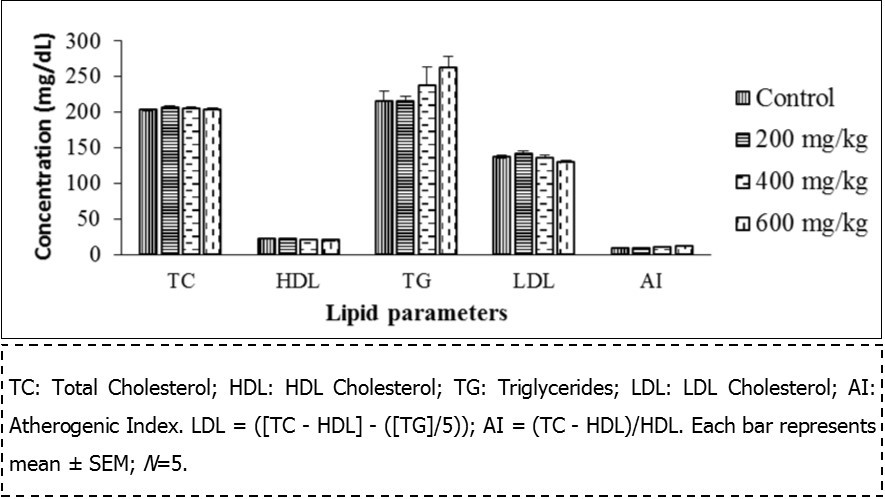

Lipid Profile

As shown in Figure 1, administration of the extract for 28 days in female rats did not alter the lipid profile except for a reduction of HDL cholesterol at a dose of 600 mg/kg. (From 20.08 ± 0.67 to 18.2 ± 0.32, p ˂ 0.05). Whereas this administration had no effect on the lipid profile of the male rats (Figure 2).

Figure 1.lipid profile of female rats

Serum cholesterol and triglycerides are largely regulated via synthesis in the liver. Changes in the levels of these lipids could give information on the predisposition of the heart to cardiovascular diseases 35. The extract did not have any significant effect on the triglyceride level while HDL cholesterol was altered at the highest dose of 600 mg/kg in females. The decrease observed in the HDL cholesterol level at the highest dose (600 mg/kg) proposes the incapability of the extract to stimulate the synthesis or interfere with the feedback mechanism associated with this organ, although the mechanism of action was not justified in this study. However, it could be suggested that the extract may not predispose the animals to heart diseases, except at the highest dose. Moreover, Etame et al. 36 also found a decrease in HDL cholesterol, serum glucose, total bilirubin and transaminases activity in both sexes at 200 mg/kg with a stem bark methanol extract of HM after 28 days of administration.